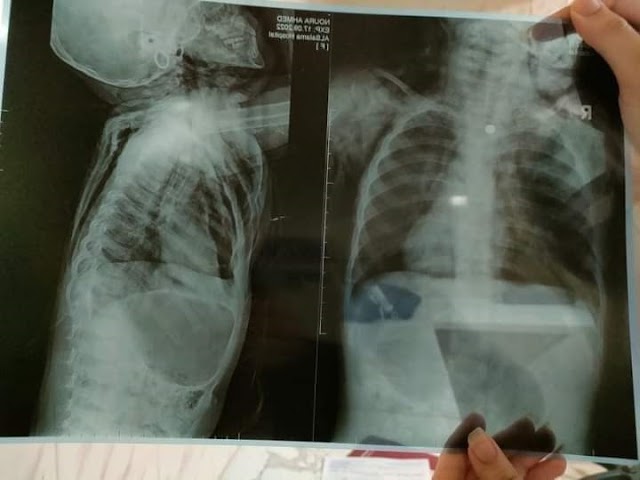

| الاشعة توضح الحالة الطبية للطفلة |

التفاصيل بحسب مصدر مسئول بمديرية الشئون الصحية في محافظة كفر الشيخ، فأكد لـ"بوابة كفر الشيخ الإخبارية"، أن غرفة طوارئ المديرية رصدت وصول طفلة عمرها سنتين إلى مستشفي سيدي سالم المركزي رفقة والديها مصابة بطلقه رش بالخطأ في رقبتها اخترقت القصبة الهوائيه ومنها إلى المرئ، والجهاز الهضمي.

وكشف المصدر عن تسبب الإصابة في حدوث إسترواح هوائي بالغشاء البلوري علي الناحيتين ما أدى إلى توقف عضله القلب للطفلهة لدقائق، ووفق ذلك جرى عمل إنعاش قلبي رئوي حتى عادت الكفلة للحياة علي جهاز تنفس صناعي، وأدوية التخدير، وانبوبة صدر علي الناحيتين.